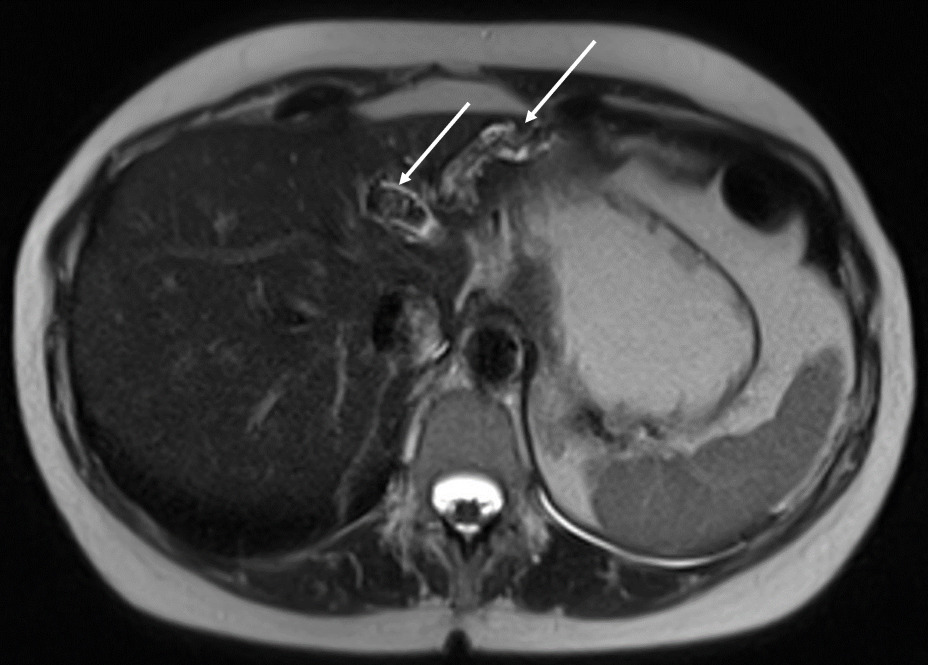

Échographie hépatique : examen clé du diagnostic

L’échographie hépatique est l’examen clé pour le diagnostic de syndrome LPAC. Celle-ci met typiquement en évidence les signes d’une microlithiase intrahépatique sous la forme d’images en « queue de comète » (échos de répétition liés à la vibration des microcristaux sous le faisceau d’ultrasons), de micro-­spots ou de « boue biliaire » (sludge) le long des canaux intrahépatiques (fig. 1A). Ces signes sont parfois difficilement identifiables, notamment en situation non sensibilisée et pour un opérateur non entraîné. Le principal diagnostic différentiel est représenté par les microhamartomes (ou complexes de von Meyenburg) qui peuvent parfois se présenter sous la forme d’artéfacts en queue de comète.9 Une échographie normale standard n’élimine pas le diag­nostic et il peut être nécessaire de répéter l’examen par un radiologue expérimenté et formé à la sémio­logie du syndrome LPAC. Moins fréquemment (5 à 10 % des cas), le syndrome LPAC peut se présenter sous la forme de vrais calculs (macrolithiases) intra- ou extrahépatiques (fig. 1B).4 Une lithiase vésiculaire n’est observée que chez un tiers des patients atteints de syndrome LPAC.